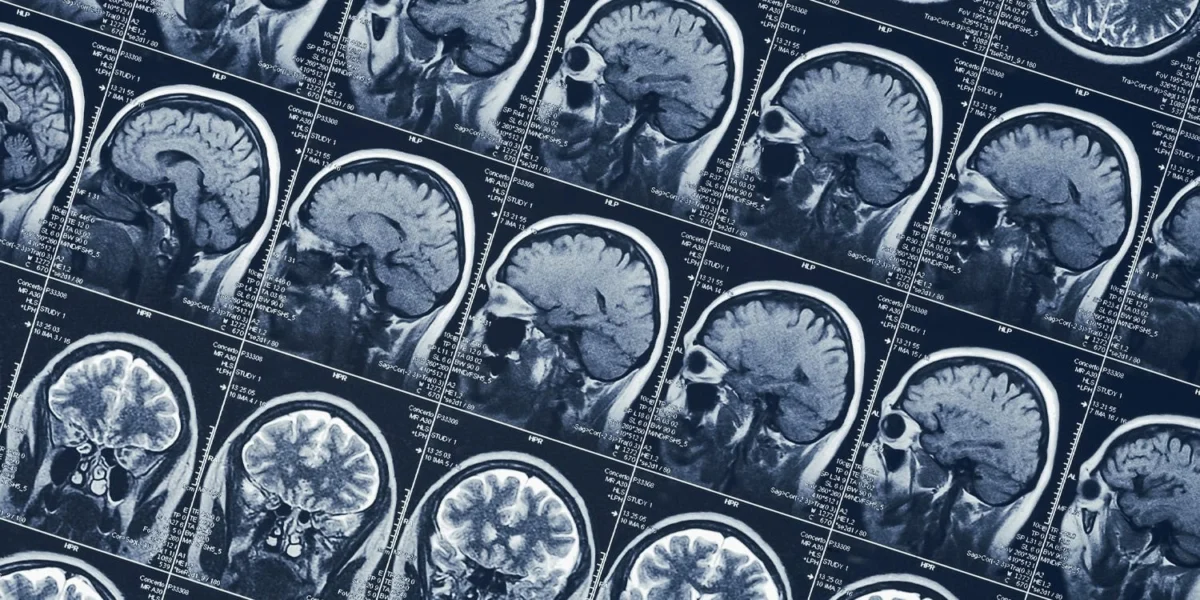

The frontiers of neuroscience have long been captivated by the mechanisms of human consciousness, particularly those states that deviate from ordinary waking awareness. A groundbreaking neuroimaging study recently published in the journal NeuroImage has provided an unprecedented look into the brain of an individual capable of voluntarily entering a transcendental visionary state. This rare, non-ordinary state of consciousness (NOC) was characterized by a fundamental reorganization of brain connectivity, where sensory inputs were suppressed in favor of heightened internal cognitive control and vivid, self-generated imagery. Led by Gabriel Della Bella and a team of international researchers, the study utilized functional magnetic resonance imaging (fMRI) to map the neural architecture of a self-induced trance, offering a unique window into how the human mind can simulate psychedelic-like experiences without the use of pharmacological agents.

The fMRI data revealed that AVP’s brain underwent a radical reorganization during the visionary state, a shift that was entirely absent in the control group. The most striking finding was the massive reduction in connectivity between the visual cortex and the rest of the brain. During the trance, the visual cortex became "uncoupled" from the auditory, sensorimotor, and thalamic regions. This effectively isolated the brain’s visual processing center from external sensory input, creating a private "theatre" where internal imagery could dominate without interference from the outside world.

Simultaneously, the somatomotor-dorsal network—responsible for processing bodily sensations and movement—disengaged from the language and auditory cortices. This neurological decoupling matched AVP’s subjective reports of losing the sensation of her physical body and experiencing a blurred boundary between her self and the space around her.

However, this was not a state of general brain deactivation. While sensory networks were suppressed, the "higher-order" networks showed increased activity and integration. Specifically, the frontoparietal control network and the salience network—areas of the brain associated with internal focus, cognitive control, and the monitoring of internal states—showed significantly increased coupling with the precuneus and the posterior cingulate cortex. These regions are central to the "Default Mode Network," which is involved in self-referential thought. This increased connectivity explains why AVP remained lucid, in control, and capable of remembering the experience in detail, unlike the often chaotic and uncontrollable nature of drug-induced "ego death."